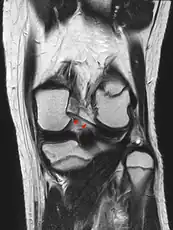

Posterior meniscofemoral ligament on MRI, coronal